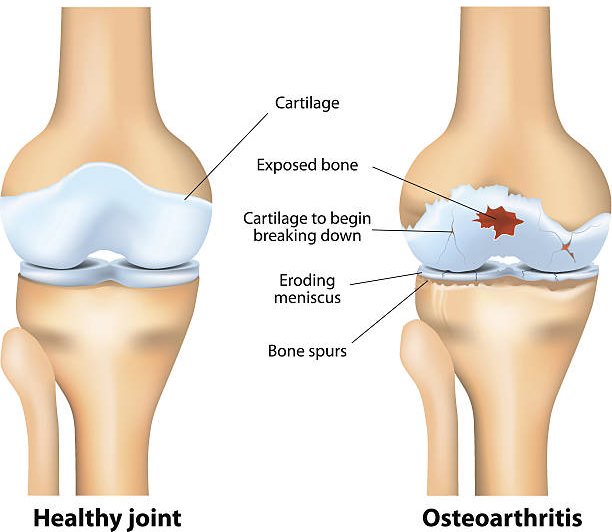

무릎연골은 무릎뼈에 가해지는 충격을 흡수하는 완충장치로 쓰면 쓸수록 닳을 수밖에 없습니다. 이러한 연골은 뼈와 유사한 성분이지만 뼈와 달리 칼슘을 함유하지 않아 뼈처럼 딱딱하지만은 않으며 탄력이 강하고 고무와 유사합니다. 이처럼 연골은 다쳐도 아프지 않기 때문에 치료를 늦추게 되고 병을 키우는 결과가 나올 수 있습니다. 하지만 연골 손상이 더 걱정되는 이유는 연골은 혈관이 없어 한번 손상되면 스스로 치유되거나 재생되지 않는다는 점입니다. 심한 경우에는 손상된 연골이 치유되지 않고 계속 퇴행하며 결국 퇴행성 관절염으로 진행됩니다.

무릎연골은 대퇴골과 경골을 각각 3~4mm 두께로 감싸 관절에 가해지는 충격을 흡수하여 관절이 원활하게 움직일 수 있도록 하기 때문에 심한 충격이나 잘못된 자세로 계속 자극하면 연골이 닳거나 부러질 수 있어 일상 생활에서 관리가 필요할 수 있지만 연골에는 신경이 없어 찢어지거나 닳아도 아프지 않아 연골이 마모되더라도 연골이 아픈 것이 아니라 아래의 뼈가 노출되어 통증을 유발하기 때문에 연골이 손상되었다면 스스로 치유되거나 재생되지 않는다는 점이기 때문에 미리미리 원인을 알고 대비해야합니다.